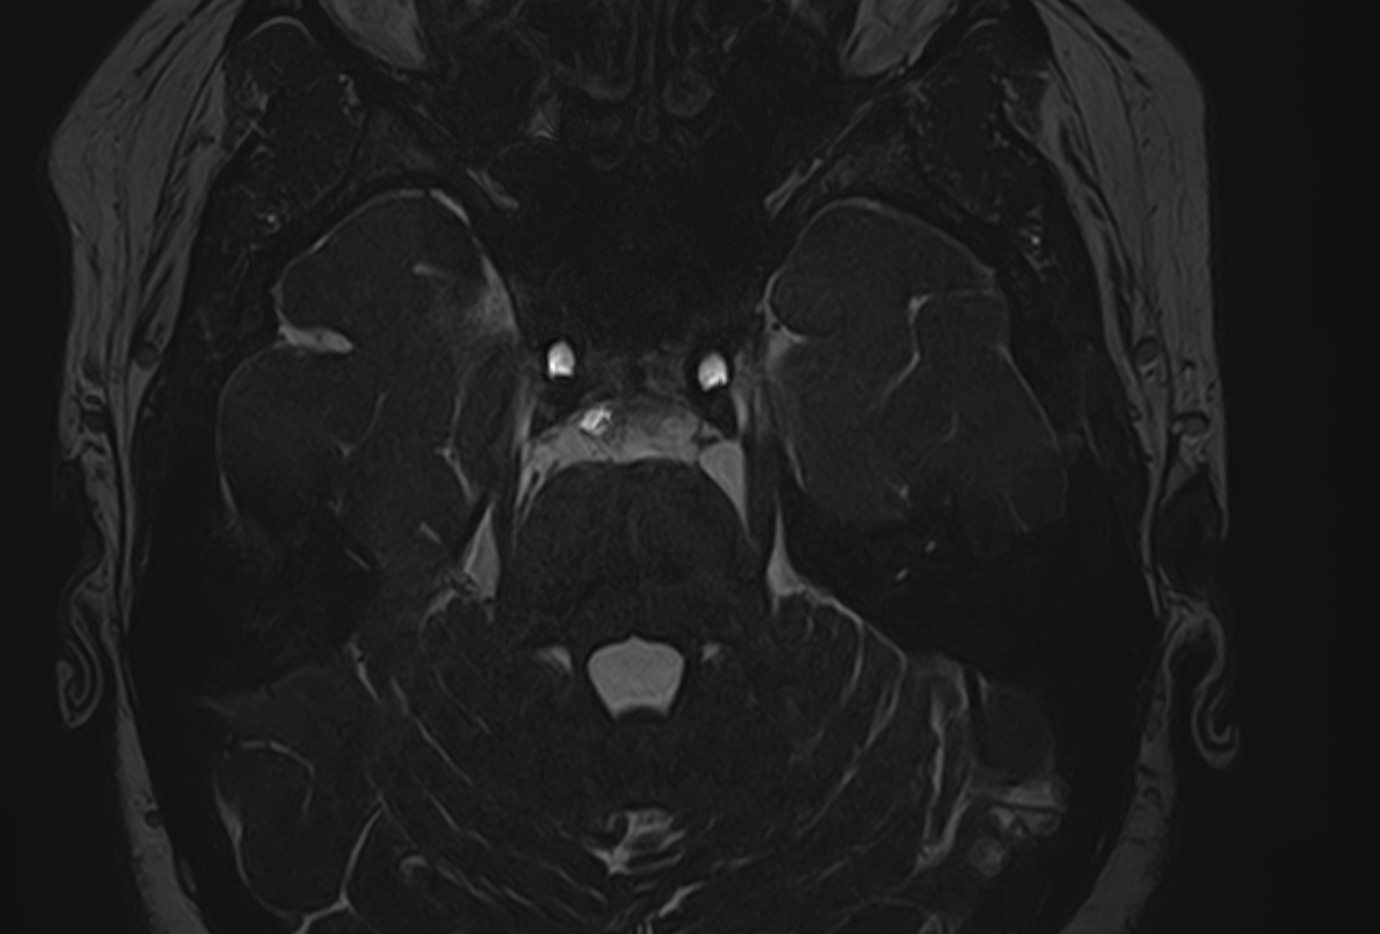

Для диагностики поражения черепно-мозговых нервов, а также оценки состояния окружающих их тканей и визуализации сосудистой сети головного мозга в клинике «Доступная медицина» проводится комплексное обследование МРТ головного мозга + черепно-мозговые нервы. Данное обследование включает в себя 2 протокола: стандартный — для оценки состояния всех структур головного мозга и специализированный — для изучения очагов поражения черепных нервов.

Оба исследования выполняются на современном высокопольном томографе экспертного класса TOSHIBA VANTAGE TITAN 1,5 Тесла, который использует разные режимы сканирования с толщиной среза от 1мм в различных плоскостях с последующей цифровой обработкой полученных данных для создания трехмерных изображений. Аппарат позволяет выявлять структурные изменения в веществе головного мозга и черепных нервах уже на начальной стадии, когда другие методы не дают результатов.

• патология нервов на фоне сосудистых проблем (вазоневральный конфликт — сдавление нерва близлежащим сосудом, также на фоне патологической извитости, аневризмы, сосудистой мальформации).